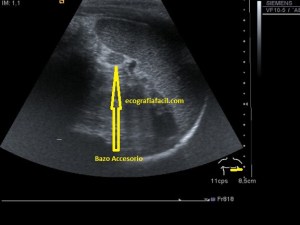

52. Protocolo de Abdomen. El Bazo.

Después del Riñón derecho, nos vamos hacia el lado izquierdo, concretamente al Hipocondrio Izquierdo, allí encontramos el Bazo.

Ecográficamente es una estructura voluminosa, hiperecogénica y homogénea que no debe medir en adultos más de 12 cms. Los vasos de la estructura se verán anecoicos.

La estructura del Bazo hace que tanto en transverso como en longitudinal el Bazo aparece ecográficamente como una estructura que estuviese reflejada en un espejo. Mira:

En Long y en Trans como si la estructura estuviese reflejada.